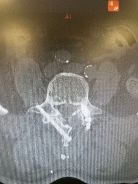

患者洪老先生,一年以来饱受左下肢疼痛麻木的困扰,反复进行着针灸、拔罐、理疗及口服消肿止痛药物等保守治疗,均效果不佳。由于症状频繁发作,持续时间长,严重影响老人家的日常生活,西安市红会医院首席专家、脊柱病医院院长郝定均及创伤与老年脊柱病区临时负责人许正伟详细了解患者相关情况后决定为患者利用微创手术彻底解除病痛。AUSS技术微创治疗手术由张正平副主任医师施行,通过在洪老先生腰部左侧的一个1.5cm的小切口,为其成功减压,切除间盘,并充分植骨后植入融合器;,利用原微创切口植入对侧经椎板关节突螺钉,既避免损伤对侧软组织、也没有增加其他切口,还达到了坚强固定和加速融合的效果,术后洪老先生恢复良好,对疗效及手术部位的身体外观也很满意。